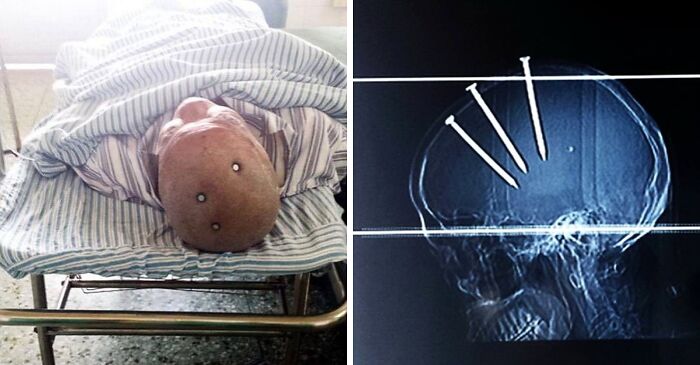

This Man Has Miraculously Survived After Apparently Hammering Three 10cm (4-Inch) Nails Into His Own Head

The 69-year-olds x-rays revealed that the nails had been hammered through his skull and into his brain – but he made a full recovery following a surgery and a 3-months stay at the hospital.

He claimed that he hammered the nails in himself and was very insistent to the doctors that the police were not called in relation to his injuries.

He made a full recovery with no major neurological deficit.